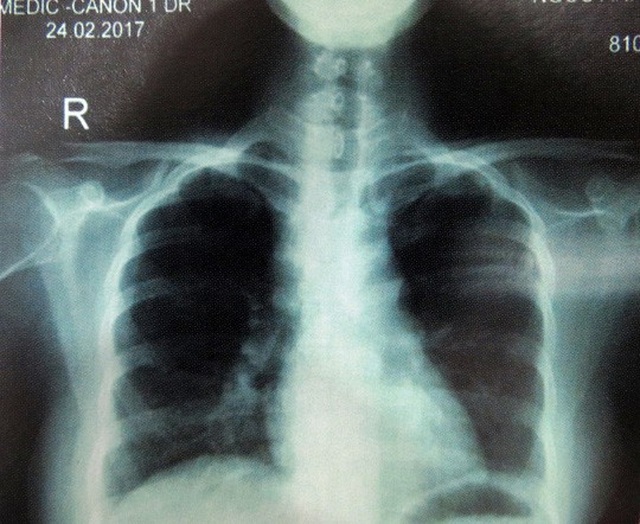

Đáng nói, sự nguy hiểm thực sự của căn bệnh không chỉ nằm trên da. Cô gái còn bị mờ mắt, chẩn đoán ban đầu là viêm màng bồ đào mắt mãn tính. Hai lá phổi cô cũng xuất hiện những nốt li ti, phì đại hạch rốn phổi phải và hạch trung thất. Tất cả các tổn thương tưởng không liên quan đó đều do bệnh siêu giả dạng gây ra.